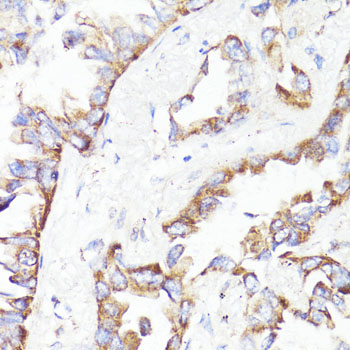

DescriptionHER2-ErbB2 Polyclonal Antibody. Unconjugated. Raised in: Rabbit.

ApplicationWB, IHC